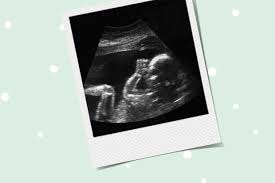

Schwangerschaft 25. Woche

Schwangerschaft 25. woche. Außerdem sind Sie jetzt im 7. Monat an welcher von weiterer Gewichtszunahme geprägt ist. Kein Wunder dass Sie zuweilen schlecht schlafen oder gar von Albträumen heimgesucht werden.

Dein Bauch nimmt weiter an Umfang zu. Schwangerschaftswoche können für die Mutter unangenehme Beschwerden auftreten. Was passiert in meinem Bauch.